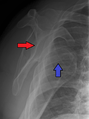

A diagnosis of shoulder dislocation is often suspected based on patient history and physical examination. Radiographs are made to confirm the diagnosis. Most dislocations are apparent on radiographs showing incongruence of the glenohumeral joint. Posterior dislocations may be hard to detect on standard AP radiographs, but are more readily detected on other views. After reduction, radiographs are usually repeated to confirm successful reduction and to detect bony damage. After repeated shoulder dislocations, an MRI scan may be used to assess soft tissue damage. In regards to recurrent dislocations, the supine apprehension test is a useful test in determining athletes who are predisposed to future dislocations.

- An anterior dislocation of the shoulder

Anterior dislocation of the right shoulder. AP X ray

Anterior dislocation of the right shoulder. Y view X ray.